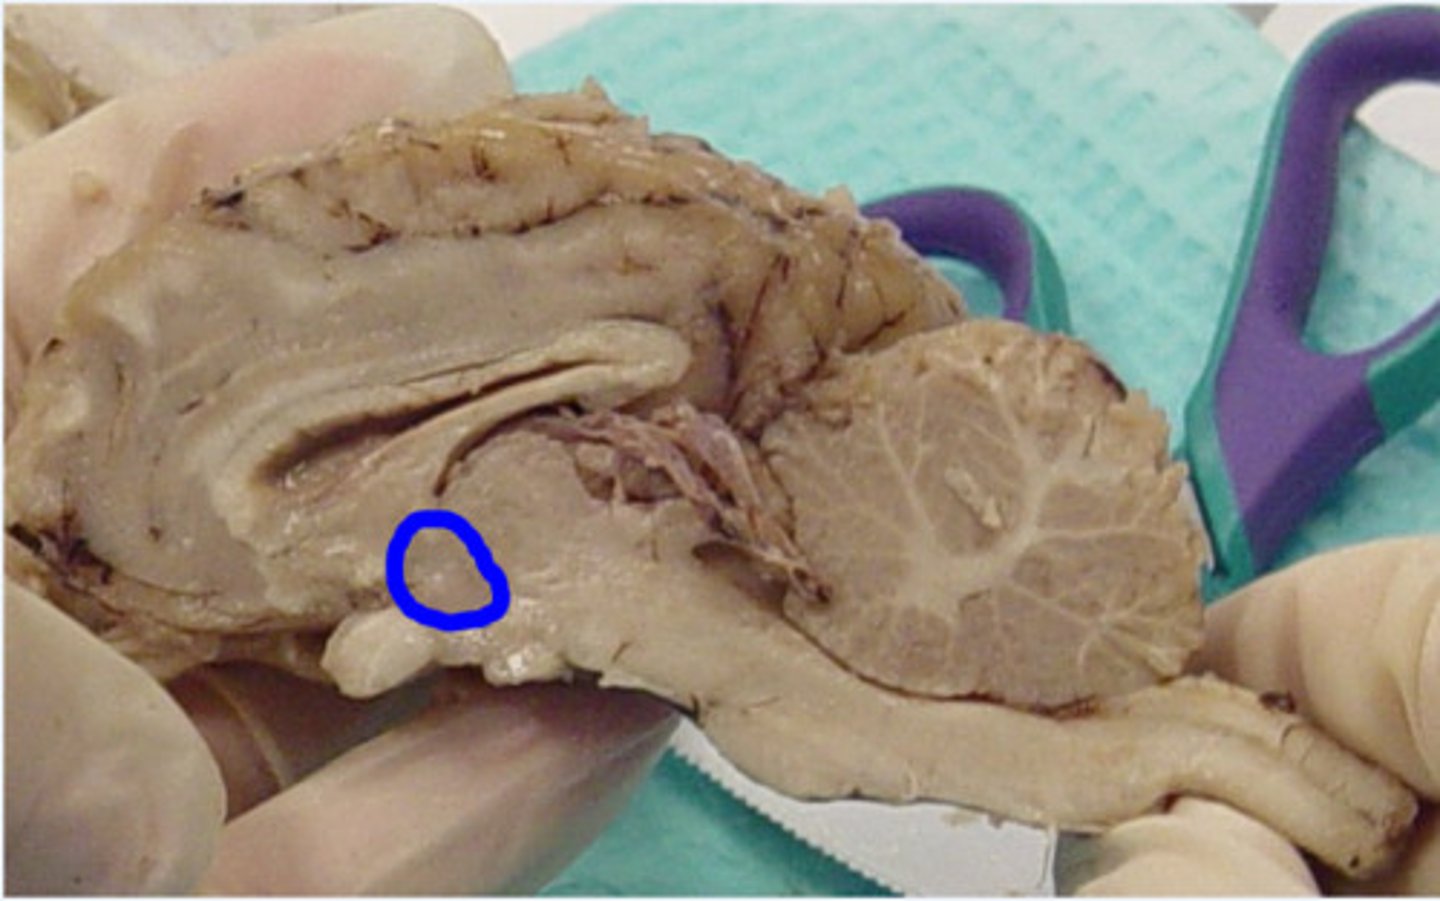

Hypothalamus

What is this?